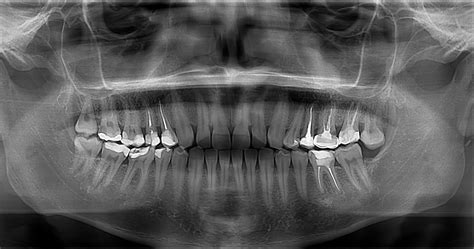

Un quiste dental es una pequeña bolsa llena de líquido, aire, o células que se forma en relación con un diente. Por lo general, se detectan en radiografías de rutina y, aunque suelen ser benignos, es importante tratarlos para evitar complicaciones.

Aunque la mayoría de los quistes dentales son benignos, en raras ocasiones, pueden volverse malignos. Por eso, es vital realizar visitas regulares al dentista, incluso si no tienes síntomas, para detectar cualquier quiste mediante un estudio radiológico y determinar su naturaleza a través de una biopsia y estudio microscópico si es necesario.